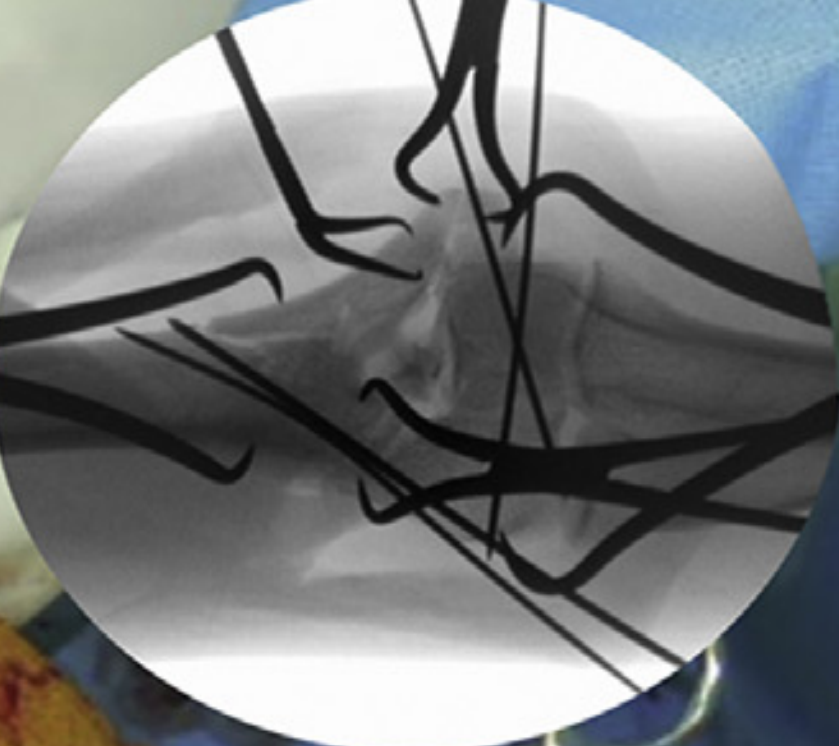

AXIA Orthopedics is developing a new solution for fracture fixation with unmatched reliability, simplicity, and versatility.

Axia's patented Reduction system:

• Works with existing surgeon flow and training

• Integrates with any implant system

• Provides precise compression of fractures and fusions

• Allows for in situ implant contouring to fit the bone

• Enables minimally invasive reduction

• Saves critical OR time

• Reduces the need for extra hands